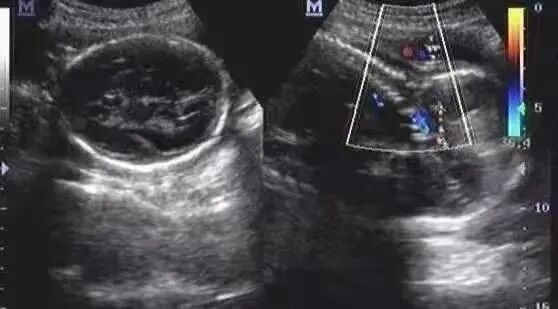

出生前超声检查提示脐带绕颈一周。

超声见胎儿颈部脐带压迹呈“W”型,超声报告结论:脐带绕颈两周。